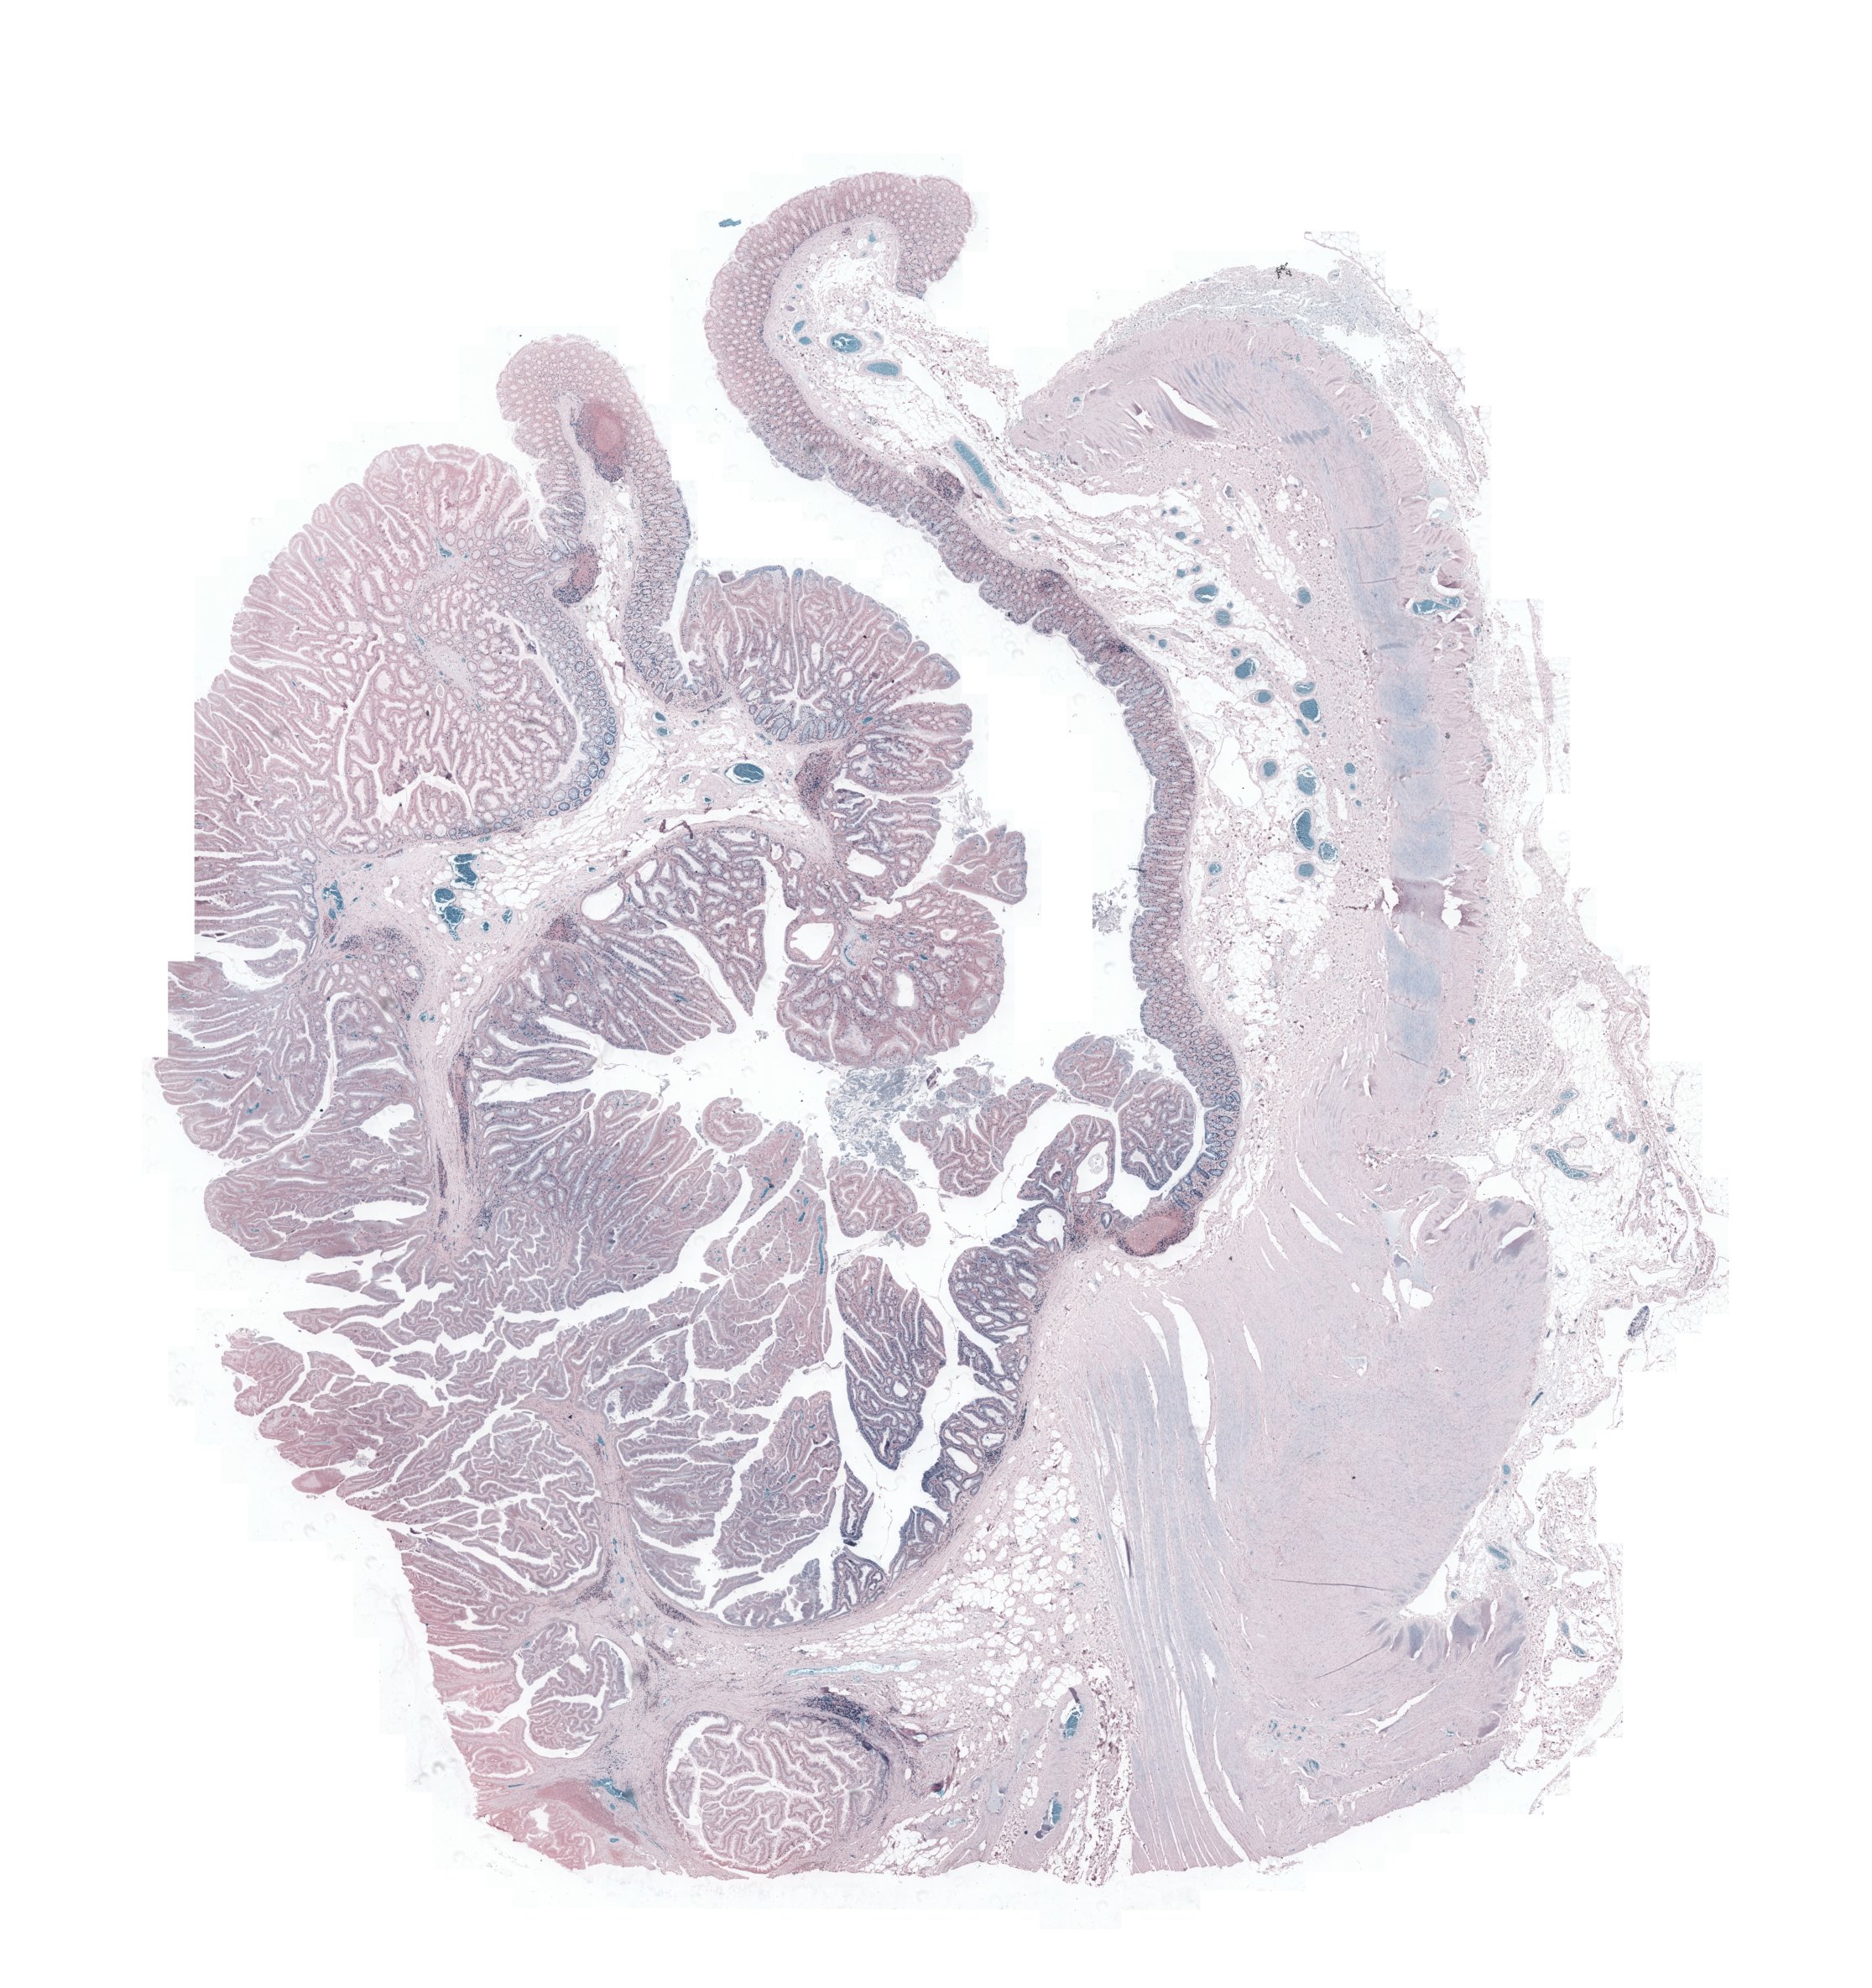

FigureΒ 2 shows the registration results for pathology images where we show the reference and floating images alongwith the misalignment images before registration and after registration using SR-Net and SR-Net. The misalignment is greatly reduced after registration using SR-Net while in the case of SR-Net there is still some resulting misalignment. This error can have significant consequences in the final diagnosis workflow. Hence the advantages of self-supervised segmentation maps are quite clear.

![]() |

| (a) | (b) | (c) | (d) | (e) |